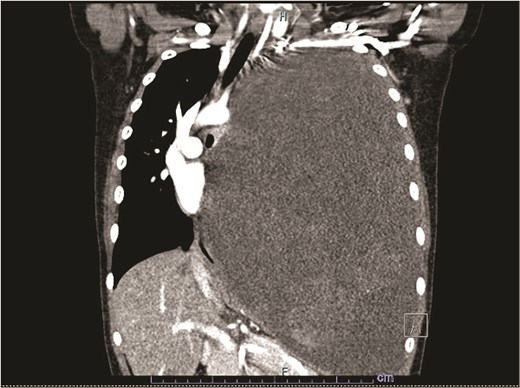

Our patient is a 10-year-old Caucasian female with a history of early adrenarche, ADHD, and COVID-19 and no past surgical history. She presented to the ED with a month-long history of persistent coughing, shortness of breath on exertion and speaking, and left-sided chest pain that began after a diagnosis of mildly symptomatic COVID-19. A physical exam revealed decreased breath sounds on the left, with a left-sided chest protrusion. A plain film and CT demonstrated a normal right lung, with a significant mediastinal shift toward the right, displacement of the heart into the right hemithorax, with complete whiteout of the left hemithorax, and demonstrating a mix of solid and cystic foci, with a round opacification at the left lung base (Figs 1 and 2). The patient underwent an uncomplicated left thoracotomy with excision of two masses, one being 22.5 × 21.0 × 10.5 cm and the other being 13.5 × 11.5 × 6.2 cm. These masses weighed 2394 g in aggregate. The specimens consisted of well-encapsulated tumors attached to the posterior aspect of the chest wall. A regional, positive lymph node measuring 3.0 × 2.2 × 1.0 cm was also resected. Due to the large size of the tumor and the requirement for clean margins, parts of the latissimus dorsi and serratus anterior muscles were also resected. By postoperative day (POD) 0, the left lung had already filled the left hemithorax, and the mediastinal shift had corrected (Fig. 3). The chest tube was removed on POD 5, and a plain film showed continued expansion of the lung to full size and resolving pulmonary edema and atelectasis (Fig. 4). The patient was discharged home on POD 5. The tumor staging was T4N1M0. The tumor was positive for vimentin, CD56, synaptophysin, chromogranin, and NSE. The tumor was negative for pancytokeratin, Cam5.2, EMA, S100, desmin, SMA, SOX10, HMB45, CD117, DOG1, CD99, PR, CD68, WT1, CD30, p53, Alk1, GFAP, and nuclear β-catenin. Next-generation sequencing showed an MGA:NUTM1 fusion, supporting a final diagnosis of high-grade MGA:NUTM1 fusion SCS. Given the size and grading of the tumor, the patient underwent adjuvant CT-RT with ifosfamide, doxorubicin, and proton beam radiotherapy, with supportive doses of MESNA and dexrazoxane for 4.5 months post-operatively. The basis of this treatment is ARST0332 Arm C [6]. Before treatment initiation, the patient underwent an uncomplicated left oophorectomy for reproductive cryopreservation. A PET/CT prior to CT-RT showed hypermetabolic activity in several areas. These included the pleural resection margin, a mediastinal lymph node concerning for metastasis versus postsurgical change, and a left axillary lymph node concerning for metastatic disease. During treatment, the patient contracted human metapneumovirus and rhino/enterovirus, resulting in febrile neutropenia. The patient was successfully treated with blood and platelet transfusions and pegfilgrastim. Upon completion of CT-RT, PET/CT imaging showed no evidence of residual disease, with minimal focal hypermetabolic activity as compared to the previous imaging (Fig. 5).